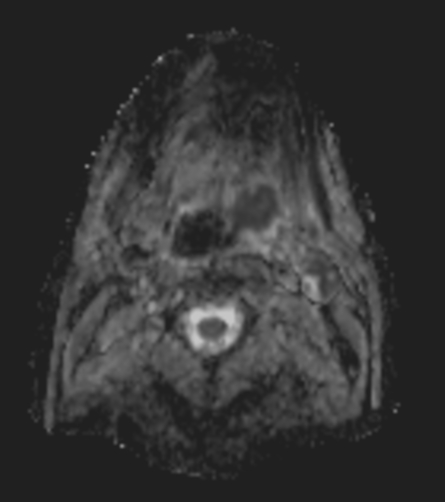

A 75-year-old male with oropharynx squamous cell carcinoma in the left tonsil region with extension into the soft palate, caudal border lower tonsil region, no midline crossing. On the left side in the neck there are also three enlared lymph nodes on level 2 and 3 with central necrosis and signs of limited extracapsular extensionn, T2N2b. Patient underwent MRI simulation in the radiotherapy (5-point) positioning mask in Ingenia MR-RT 3.0T using the Flex coils in combination with integrated Posterior FlexCoverage coil.

DWI SPIR (b800)